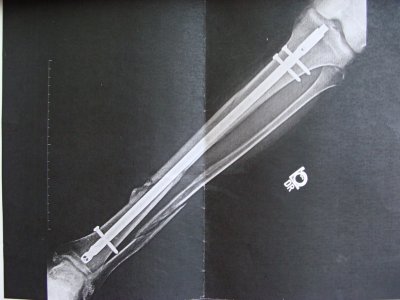

Всё последующеие два месяца я и провёл в этом ботинке. Его можно было снимать и одевать, для того чтобы мыть ногу. Периодически меня вызывали врачи на визит, делая рентген и наблюдая за процессом заживления костей. Где-то через полтора месяца мне разрешили применять один костыль для ходьбы (это скорее всего было их требование). Затем через две недели вообще без костылей. Прошло две недели, как я проходил без костылей, после обследования они мне разрешили ходить в обычной обуви, всмысле без того гипсозаменяющего приспособления.Вот уже почти две недели хожу без костылей и в нормальной обуви. Врачи хотели мне назначить терапию, но в связи с моим переездом, я не смог пойти на эти процедуры. Хотя врач сказал, что ничего и страшного. Вот снимок с последнего визита к врачу, 10 недель спустя после перелома:

DSC08661.JPG

DSC08663.JPG

Вопрос по поводу малой берцовой кости: судя по снимку, я вижу, что кость не срослась как следует. спрашивал врача, он сказал, что потребуется ещё время для сростания. Боюсь, что может сростись неправильно или какие то осложнения быть. Хотя когда врач прощупывал, то никаких болей не чувствовал